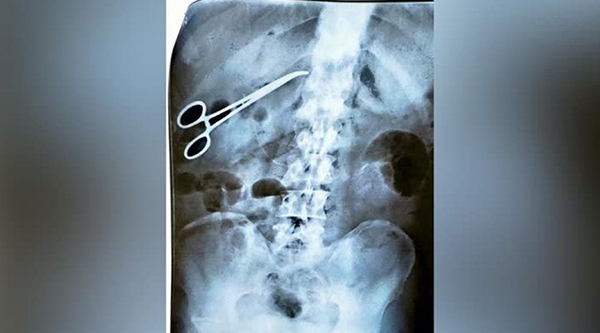

அ றுவைசிகிச்சை வெ ற்றி.. ஆனால் வ யிற்றுக்குள் க த்தரிக்கோலை மறந்த ம ருத்துவர்: அ வஸ் தையுடன் 25 நாட்கள்!

அதன்படி, திரிச்சூர் அரசு கல்லூரி மரு த்துவமனையில் அ றுவைசிகிச் சையும் செய்துள்ளார். அங்கிருந்த சீனியர் ம ருத்துவர் கவனக்குறைவாக அறு வைசிகி ச்சைக்குப் பயன்படுத்திய கத்தரிக்கோலை வயிற்றுக்குள்ளேயே வைத்து தைத்ததால் அதை அகற்ற மீண்டும் அறு வைசிகி ச்சை செய்துள்ளனர்.

இதைக் கேட்ட எங்களுக்கு சந்தேகம் எழுந்தது. அதனால் வேறொரு தனியார் மரு த்துவ மனைக்கு சென்று எக்ஸ்ரே எடுத்துப் பார்த்தபோதுதான் வயிற்றுக்குள் கத்தரிக்கோல் இருப்பது தெரிய வந்தது. தனியார் மரு த்துவமனையிலேயே அறு வைசிகிச் சை செய்து க த்தரிக்கோலை வெளியே எடுத்தோம்.